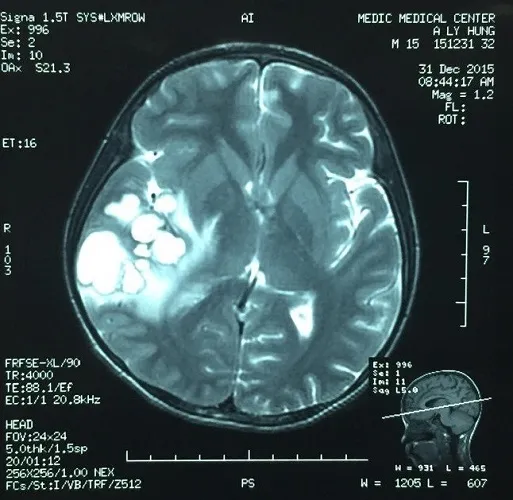

Ổ ấu trùng sán dải heo (vùng trắng bên trái) trong não bệnh nhân.

Bên cạnh đó, kết quả chụp MRI não em thấy tổn thương không điển hình cho một khối u và không điển hình cho tổn thương của ký sinh trùng. Tuy nhiên, BV quyết định phẫu thuật khối tổn thương của ký sinh trùng do nó tăng áp lực nội sọ khiến em đau đầu nhiều và yếu nửa người.

“Kết quả lấy ra một khối sang thương đường kính 5 cm (to bằng trái chôm chôm) có nhiều nang, bên trong chứa dịch, trong lòng nang thương tổn như chứa ấu trùng. Kết quả giải phẫu bệnh lý là ấu trùng sán dải heo” - BS Trí nói.